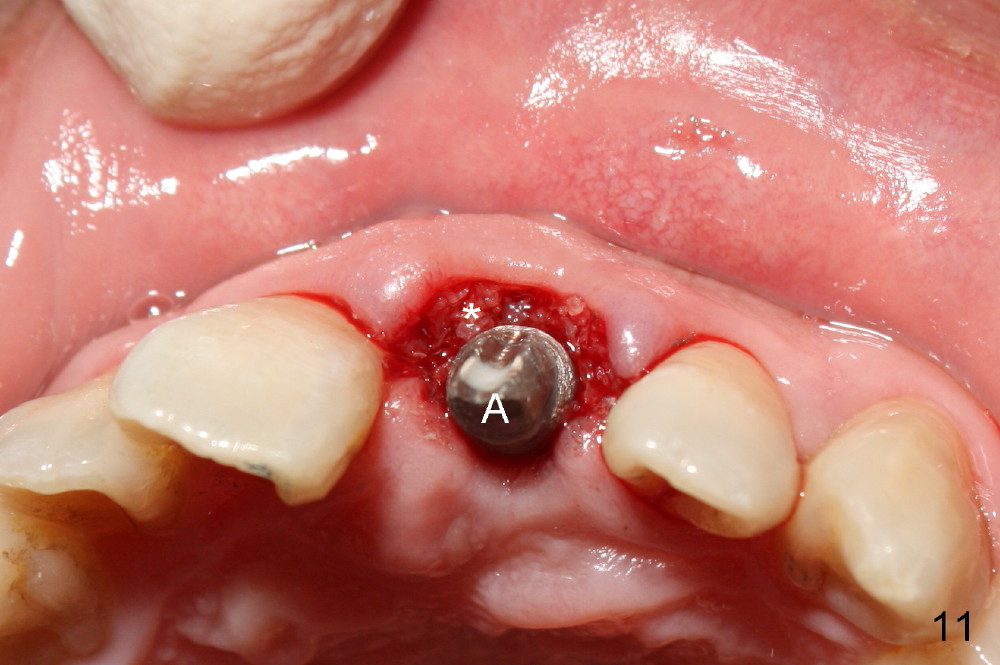

Bone expansion allows the implant (Fig.9 I) to have primary stability (insertion torque between 50 and 60 Ncm), since the cortex of the incisive canal is apparently intact.  Allograft is placed in the labial gap (Fig.10, 11 *) following installation of the abutment (A).  Finally an immediate provisional (Fig.10,12 P) is cemented.  Fig.13,14 are taken 8 days postop.  The patient returns 3 months postop (Fig.15,16).  Osteointegration appears to have occurred (Fig.15 arrowheads) and is more obvious 9 months postop (Fig.17).